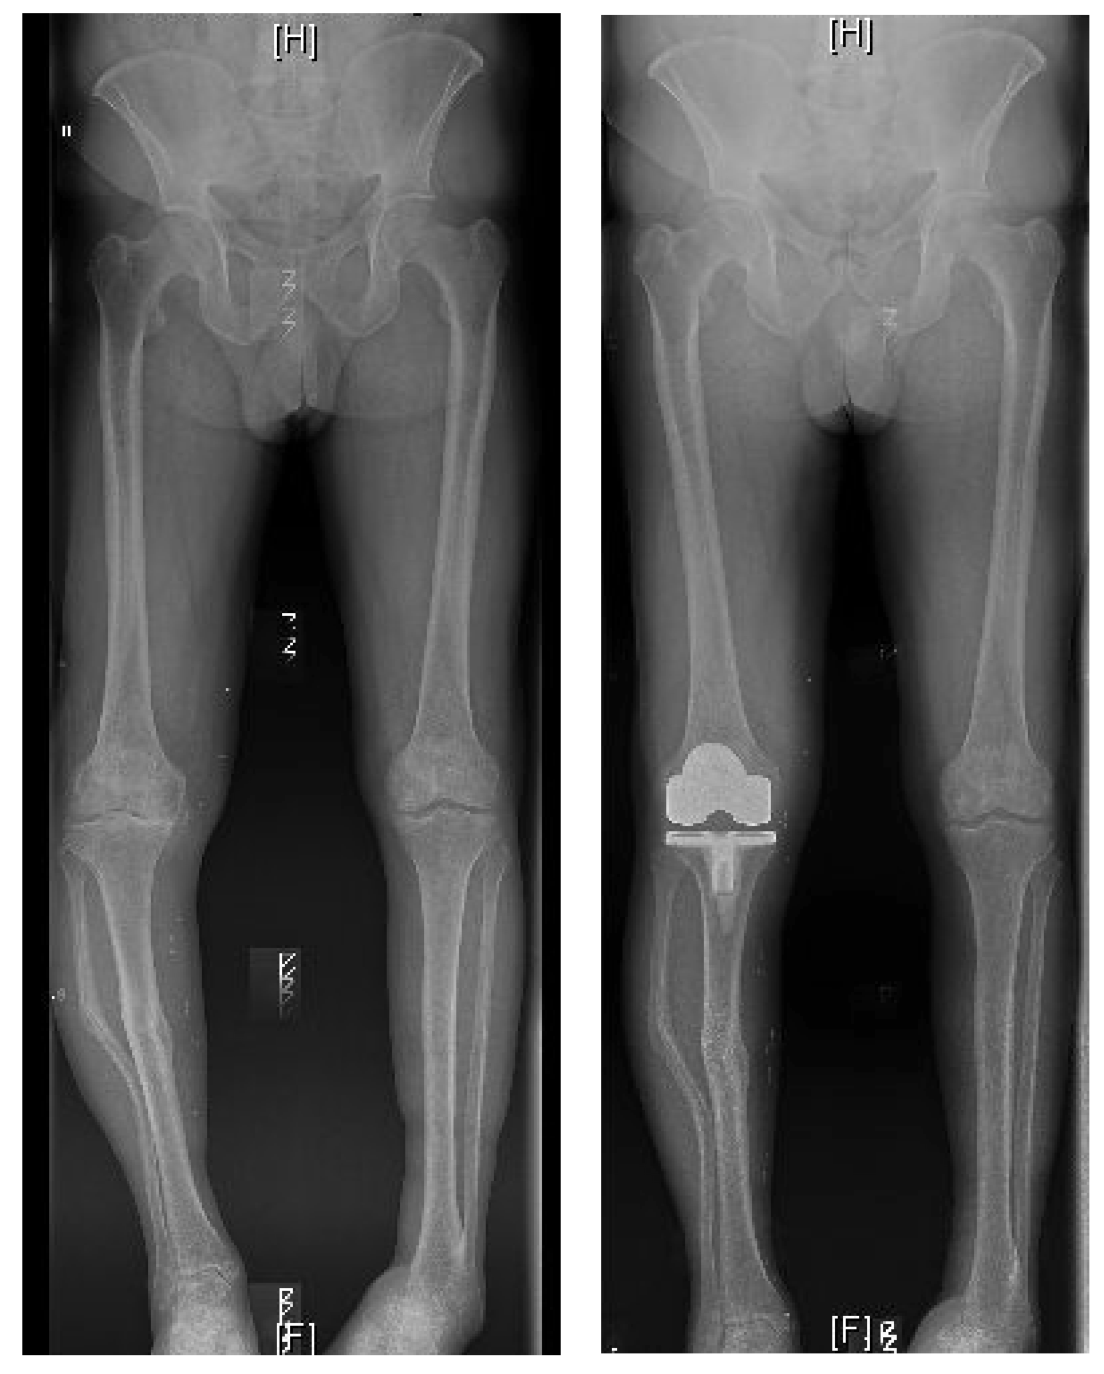

TOTAL KNEE REPLACEMENT

"Able to walk pain-free again"

I had a knee replacement operation in October 2015 in the Sports Surgery Clinic and I would like to share my experiences with other people. I had my pre-assessment 3 weeks prior to my operation which was done so efficiently and where all information was relayed back to me very shortly afterwards. During the consultation with Mr. Mihai Vioreanu there was nothing left for me to ask as he explained the full procedure very clearly and he informed me about everything in full detail.

"If you need a knee replacement go for it"

I waited 7 years and am sorry I did. I got my new knee in Sept 2017 with Mr. Vioreanu and never looked back! It is the best thing I have done. Mr Vioreanu and his staff are so friendly and professional. Follow up is wonderful and everything seems easy and natural to them.

"I knew from an early stage that I was in safe hands"

I would like to thank you for the excellent and professional service that was provided in dealing with my knee surgery back in May of 2015. Your wonderful personality made me feel at ease and I knew from an early stage that I was in safe hands. After my surgery, your daily visits gave me the confidence and assurance to get back on my feet, albeit on crutches, and within 3 days I was home.

BILATERAL TKR SURGERY

"Back to playing bowls pain free"

At 82 years of age I had both my knees replaced at Santry Sports Clinic by Mr. Mihai Vioreanu, who came highly recommended. I had my first consultation with Mr.Vioreanu in mid-july 2016, and was very impressed with how he explained the whole procedure to me, including the emphasis he put on the importance of doing the exercises, both pre and post op. Very down to earth, and made me feel, ‘ok let’s go, let’s get on with it’.

BILATERAL SIMULTANEOUS KNEE REPLACEMENTS

"Pain free and no limp at 3 months"

I am 40 years old and Mihai performed bilateral, simultaneous full knee replacement surgery for me just over three months ago. The surgery was a complete success. I now walk pain free and without any limp. I am living my life to the full again. I will be forever grateful for the outstanding level of care I received from Mihai and his clinical and admin teams.